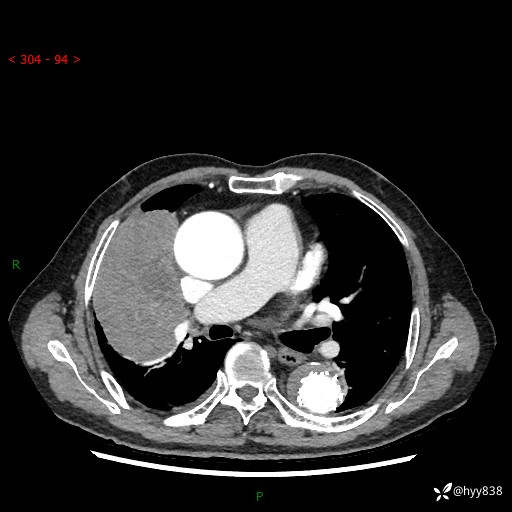

胸部CT平扫